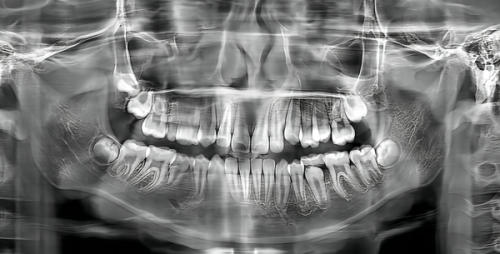

在北京,口腔健康問題困擾著不少人,而選擇一家合適的口腔醫院至關重要。北京中騰口腔醫院就是一家頗受歡迎的口腔機構,今天咱們就來聊聊怎麼去這家醫院,同時也了解一下北京東城區的口腔收費情況。

2025年北京東城區牙齒的費用因材質、品牌、手術難度及醫院級別等因素而異。以下是大致的費用區間:

| 項目 | 費用區間 |

|---|---|

| 2025年02月烤瓷牙套 | 350元 - 590元左右 |

| 2025年02月補牙 | 70元 - 210元左右 |

| 2025年02月兒童牙科 | 150元 - 370元左右 |

| 2025年02月拔牙 | 90元 - 2198元左右 |

| 2025年02月種植牙 | 1888元 - 8950元左右 |

從價格走勢來看,2025年1 - 6月北京東城區牙齒參考費用有一定波動,1月參照費用190元,2月參考收費210元,3月參照收費220元,4月參考費用160元,5月參考價格210元,6月參照價格220元。